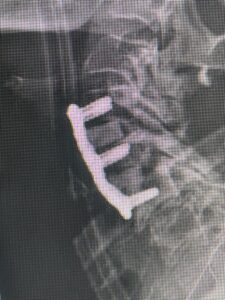

(Fig 3) lateral intraoperative cervical x-ray demonstrating good alignment after C4-C6 anterior cervical discectomy and interbody fusion with plate. Note the interbody grafts help load-share the plate in this patient with severe osteoporosis